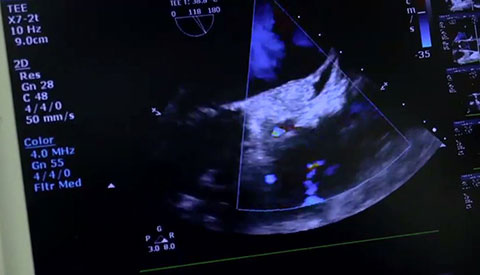

استخدام Live xPlane لتقييم النتائج. ما يتم عرضه هنا: عدم وجود تسريب في المنطقة المجاورة للصمام.